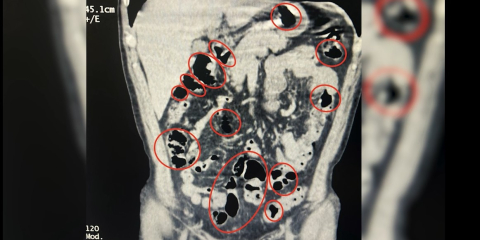

Özcan ÇİRİŞ/BİTLİS, (DHA)- BİTLİS'te üzerlerinde yapılan aramada ve mide ile bağırsaklarında toplam 50 kapsül halinde 385 gram metamfetamin ele geçirilen 2 şüpheli gözaltına alındı.

İl Emniyet Müdürlüğü Narkotik Suçlarla Mücadele Şube Müdürlüğü ile İstihbarat Şube Müdürlüğü ekiplerinin çalışması sonucu Tatvan ilçe girişinde durdurulan bir yolcu otobüsünde seyahat eden yabancı uyruklu 2 kişinin üzerinde arama yapıldı. Aramalarda şüphelilerin üzerinde 36 kapsül içerisinde uyuşturucu ele geçirildi. Tatvan Devlet Hastanesi’ne götürülen şüphelilerin burada yapılan röntgen ve tomografi incelemelerinde de mide ve bağırsaklarında yabancı cisimler tespit edildi. Tıbbi müdahale sonucu şüphelilerin yuttuğu 14 kapsül çıkarıldı. Toplam 50 kapsül halinde 385 gram metamfetamin ele geçirilen 2 şüpheli gözaltına alındı.